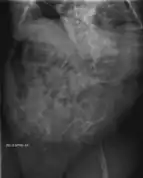

Les aspects radiographiques de l'os contribuent au diagnostic.

Diagnostic radiologique

On observe une transparence excessive des os ainsi que des déformations sur les clichés radiologiques[7]. Ces déformations sont principalement constatées au niveau de :

- la partie diaphysaire de l’os : une corticale diaphysaire mince, une crosse au niveau des os longs ainsi que la présence de plusieurs cals osseux ;

- la hanche avec une protrusion acétabulaire c'est-à-dire une malformation associant une hanche trop profonde et des amplitudes articulaires diminuées ;

- des pieds avec des pieds plats et en valgus c'est-à-dire les membres qui s’écartent vers l’extérieur par rapport à l’axe du corps ;

- des membres supérieurs avec une déformation supérieur à 30° ;

- du crâne avec des os wormiens c'est-à-dire des petits os situés à l'intérieur de divers os constituant le crâne (occiput, pariétal, temporal…) présents en nombre plus important que la normale ;

- du rachis et du thorax avec un thorax plus bombé que la normal et des modifications au niveau des vertèbres telles que des tassements de certaines vertèbres, des vertèbres biconcaves, des scolioses… Lors de fractures, le siège se situe principalement au niveau des membres inférieurs et des vertèbres.